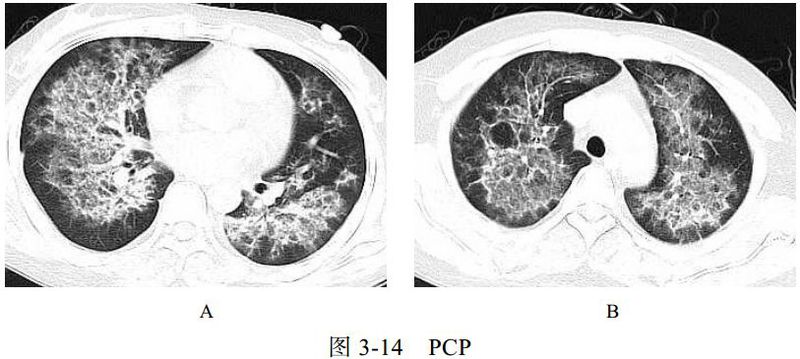

卡氏肺孢子虫肺炎(PCP)是艾滋病患者最主要的机遇性感染之一。卡氏肺孢子虫引起Ⅰ型肺泡上皮细胞损害、Ⅱ型肺泡上皮细胞增生和间质性肺炎等病理改变,可导致肺间质性纤维化。临床表现为进行性呼吸困难、咳嗽、发热,病程持续数周或数月。PCP 相关检测查找卡氏肺孢子虫病原体。艾滋病患者免疫力极低,常合并其他感染,如结核、真菌等。

影像学表现:

(1)广泛或局限性磨玻璃样密度影,以肺门周围为主,有融合趋势(图 3-14A)。

(2)慢性及复发的病例可引起小叶间隔增厚及网格影。

(3)可出现囊性病变(图 3-14B)、自发性气胸及肺实变影。

(4)常不伴肺门及纵隔淋巴结肿大和胸腔积液。